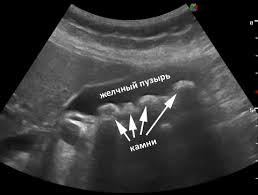

Классической ультразвуковой картиной желчного конкремента являются плотная структура, визуализация только его передней поверхности и акустическая тень на всю ширину камня. При перемене положения тела конкремент смещается. При визуализации конкрементов нужно помнить, что они располагаются в наиболее отлогих местах. Если пациент на исследование пришел самостоятельно, то наиболее вероятным положением конкрементов является область дна, если доставлен на каталке, возможно любое положение камней, в том числе в кармане Гартмана. Для тщательного поиска желательно переменить положение тела пациента: подвижный камень передвинется, фиксированный камень останется на месте. Причинами фиксации может быть ущемление в шейке или формирование местных изменений желчного пузыря в области конкремента. Размеры желчных конкрементов бывают различные. Наименьшие конкременты, которые могут быть визуализированы на современных диагностических приборах, имеют размеры до 2–3 мм. Крупные конкременты могут занимать весь просвет пузыря, последний утрачивает свою работоспособность. Крупные конкременты могут травмировать стенку пузыря, приводить к формированию пролежней, считаются предрасполагающим фактором развития рака желчного пузыря. Мелкие конкременты наиболее опасны, так как могут войти в пузырный проток, диаметр которого около 3 мм, царапнуть стенку и привести к спазму протока. Со спазма протока начинается развитие желчной колики. Определенные трудности представляет диагностика множественных конкрементов, прилегающих друг к другу и заполняющих весь просвет пузыря, желчь в нем отсутствует. В этом случае при ультразвуковом исследовании видна передняя стенка пузыря, за ней определяется зубчатая поверхность переднего ряда камней, дистальнее определяется акустическая тень на всю ширину пузыря. Определить размеры каждого из конкрементов в таком пузыре не представляется возможным, обычно достаточно указать размер наибольшего и наименьшего конкрементов. Иногда возникают сложности при визуализации очень мелких конкрементов, которые имеют маленькие размеры и находятся на дне, или передвигаются в виде маленькой «дорожки камней» с тенями, сливаясь с газосодержащими петлями кишечника у стенки пузыря. Такие конкременты требуют внимания и тщательного полипозиционного исследования. Конкременты могут выходить из желчного пузыря в общий желчный проток, это приводит к увеличению его диаметра. При ультразвуковом исследовании, на фоне желчи, в протоке визуализируется конкремент различных размеров, обычно соответствующих размеру холедоха. Камни холедоха могут не затруднять отток желчи, могут быть вентильными, при определенном повороте приводить к перекрытию просвета, или полностью перекрывать его, приводя к развитию гипертензии желчевыводящих путей и механической желтухе. Конкременты в холедохе могут быть множественными, прилегать друг к другу, иметь фасетчатое строение и полностью закупоривать просвет. Камень может быть ущемленным в дистальной части холедоха и в ампуле большого дуоденального соска, также приводя к гипертензии желчевыводящих путей и развитию холестаза. При ультразвуковом исследовании конкремент в ампуле или дистальной части холедоха лучше визуализируется на срезах головки поджелудочной железы в интрапанкреатической части холедоха. Он лоцируется как акустически плотная структура с тенью, заполняющая просвет расширенного холедоха.